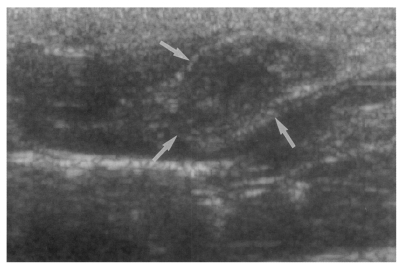

Fig. 6

Sonogram of a rat in the reinfection I group 6 weeks after reinfection (13 weeks after treatment), showing an empty dilated bile duct confluence (arrows). Neither worms nor desquamated materials were found.

High echogenicity closely packed at the dilated bile duct confluence was seen in all rats in the primary or secondary infection control groups; however, this was seldom noted in the reinfection I (n = 1) and reinfection II groups (n = 0) (p = 0.005 and p = 0.001, respectively) (Fig. 6). The echogenic mass was found to be composed of clusters of worms and desquamated materials by pathological examination. Small echogenic foci were noted in the dilated bile duct confluence in the infection following immunization group. These also represented worms and desquamated materials (Fig. 7). In the reinfection I and II groups, the degree of dilatation of the bile duct confluence on the last follow-up sonograms at 26 weeks after reinfection were noted to be slightly milder than those at 6 weeks after reinfection, but this was not significant (p = 0.266 and p = 0.431, respectively) (Table 2).

However, no report has been issued on the sonographic findings of clonorchiasis in rats. The present study first reports that dilatation of the bile duct confluence is associated with high echogenicity by highresolution sonography, and well reflects pathological features. No rat showed such a finding unless rat was infected by C. sinensis. The present study shows that sonography is a good noninvasive radiologic tool to determine the presence of worms in rats, particularly in cases with a moderate or heavy worm burden. In the present study, sonography showed moderate or marked dilatation of the bile duct confluence and of the extrahepatic bile duct in rats with an active (present) or a previous infection. However, the hyperechoic mass formed by worms and desquamated materials in dilated duct was found only in rats with an active infection.